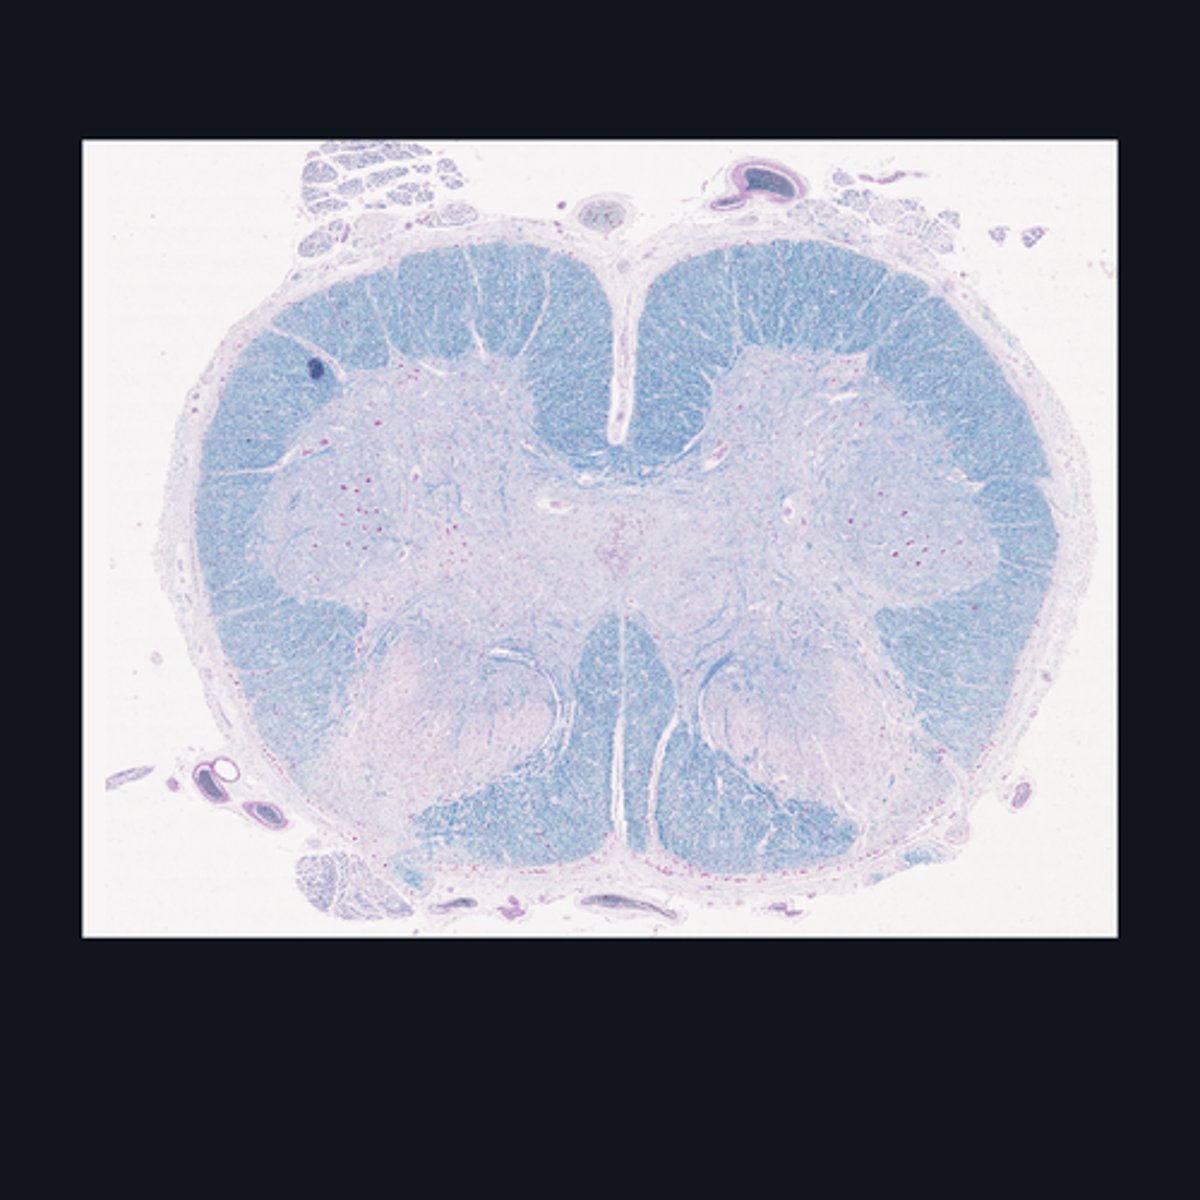

Identify the region of the spinal cord in the given image.

FALSE

T or F: The white matter in this region of the spinal cord is larger than the white matter in the thoracic region of the spinal cord.

Upper Cervical region

Identify the region of the spinal cord in the given image.

(top to bottom)

White matter

Ventral horn of gray matter

Central canal

Central Commissure

Dorsal horn of the gray matter

Dorsal Midline Sulcus

Identify the structures found in the upper cervical region of the spinal cord.